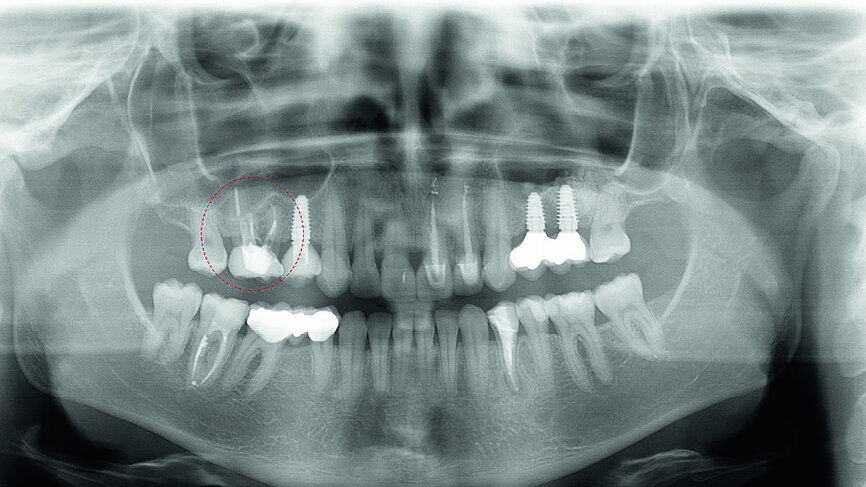

In November 2017, a 39-year-old female patient came to an initial appointment at White Clinic owing to tooth pain (tooth #16). A clinical and radiographic examination were performed, including a periapical radiograph, CBCT scan (Carestream 9500, Carestream Dental), and intra- and extraoral photographs (Figs. 1–3).

In the clinical and radiographic evaluation, it was observed that tooth #16 presented an invasive cervical resorption at the mesiobuccal root. The treatment plan established was dental extraction with immediate implant placement. The tooth had been previously re-treated endodontically and restored with a definitive ceramic crown. Due to the current situation of the tooth, although the protocol in White Clinic is to preserve teeth, it had indication for immediate extraction. Also due to the lack of time, our digital team was not able to produce a surgical guide for the implant placement. Therefore, the treatment plan included a surgical phase and a digital prosthetic phase.